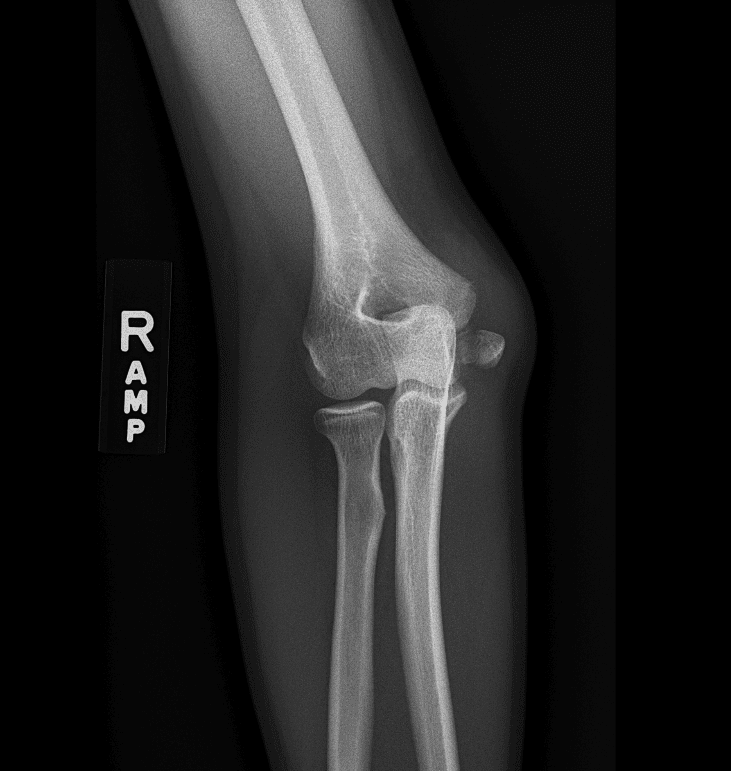

Simulates call by including subtle or difficult cases and some normals.

40 cases